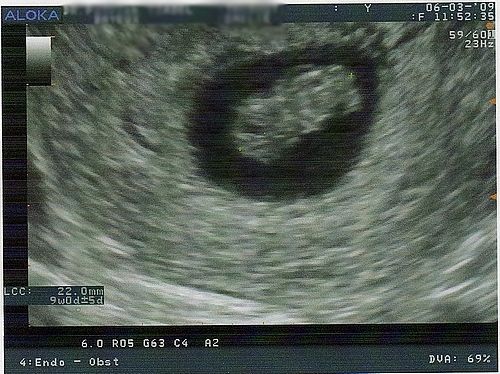

Par emy50 : le 10/03/09 à 16:16:20

| Dire merci | Voici notre petit bout qui pousse, malgré l'angoisse du premier trimestre tout se passe bien. Il fait 22 mm. On a pour la première fois entendu son petit coeur battre prochaine écho le lundi 30 Mars![]() Message édité le 10/03/09 à 16:16 |

Par emy50 : le 10/03/09 à 16:47:10

| Dire merci | Kaliméro j'étais à exactement 8semaines et 5 jours quand je l'ai faite ![]() riri facettie sa va viendre soyez patiente |